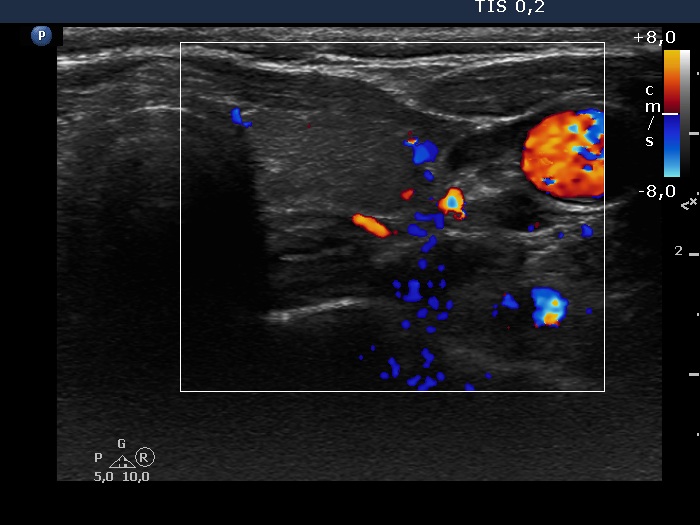

Left lobe, transverse view, color Doppler mode. The vascularization is average.